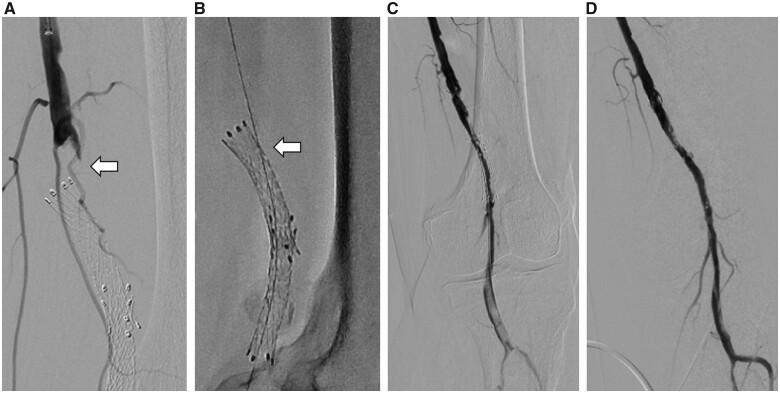

A 72-year-old man was admitted to our hospital with acute rest pain and coldness of his left leg; he was diagnosed with acute limb ischaemia. The angiogram demonstrated a fractured stent as well as stent occlusion in the left distal SFA. The guidewire could pass only through the stent-strut because of stent fracture. Fortunately, balloon angioplasty through the stent-strut and thrombolysis achieved successful revascularization. Thereafter, an additional stent was implanted in an attempt to manage the fractured and deformed stent. To obtain sufficient expansion of the additional stent, an experimental study to examine the balloon diameter and pressure to break the stent-strut was performed. Based on the results of the experiment, the stent-strut was successfully broken, and the additional stent was expanded through the stent-strut on the second intervention.

一名72岁男性因左下肢急性静息痛和发凉入院;诊断为急性肢体缺血。血管造影显示左股浅动脉远端有一个断裂的支架以及支架闭塞。由于支架断裂,导丝只能穿过支架小梁。幸运的是,通过支架小梁进行球囊血管成形术和溶栓实现了成功的血管再通。此后,为处理断裂和变形的支架植入了一个额外的支架。为使额外的支架充分扩张,进行了一项实验研究以检测破坏支架小梁所需的球囊直径和压力。根据实验结果,成功破坏了支架小梁,在第二次干预时额外的支架通过支架小梁得以扩张。